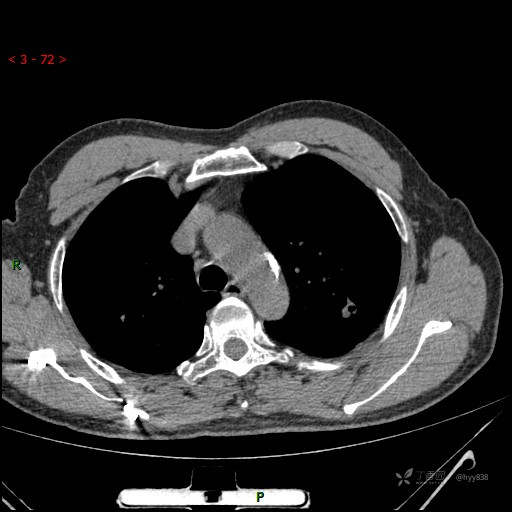

又遇恼人的肺结节,囊腔 VS 空洞 VS 空泡,欢迎讨论---结果公布~

简要病史:患者半月前因双眼翼状胬肉于我院眼科就诊行手术治疗,完善胸部CT发现左肺结节,未行特殊处理,偶有刺激性干咳,每于受凉后及饮冷水后发作,休息后可自行缓解,无发热、恶心呕吐、胸痛咯血,现为求进一步诊治,于我院就诊,门诊以“左肺结节”收入我科。 起病以来,患者食欲尚可,大小便正常,睡眠、精神可,体力、体重无明显变化。

临床诊断:肺结节

胸部CT平扫